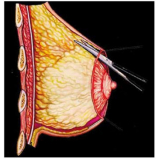

Mamoplastia de Elevação

Se você não sabe onde encontrar bons profissionais, equipe médica compromissada e sempre pronta a atender bem o seu cliente? Pois não se preocupe mais pois a FF Cirurgia Plástica coloca à disposição do cliente a possibilidade de contratar assistência médica pertinente que o possibilite submeter-se à mamoplastia de elevação.

Não pense duas vezes: conheça o consultório médico que realiza mamoplastia de elevação!

Praticidade pensada no que é mais adequado às necessidades do cliente, com profissionais de saúde por perto, levando maior segurança e eficiência até você. Busque com essa equipe todas as informações que precisa e saia satisfeito e tranquilo! Qualidade e bom atendimento você encontra de excelência na FF Cirurgia Plástica.